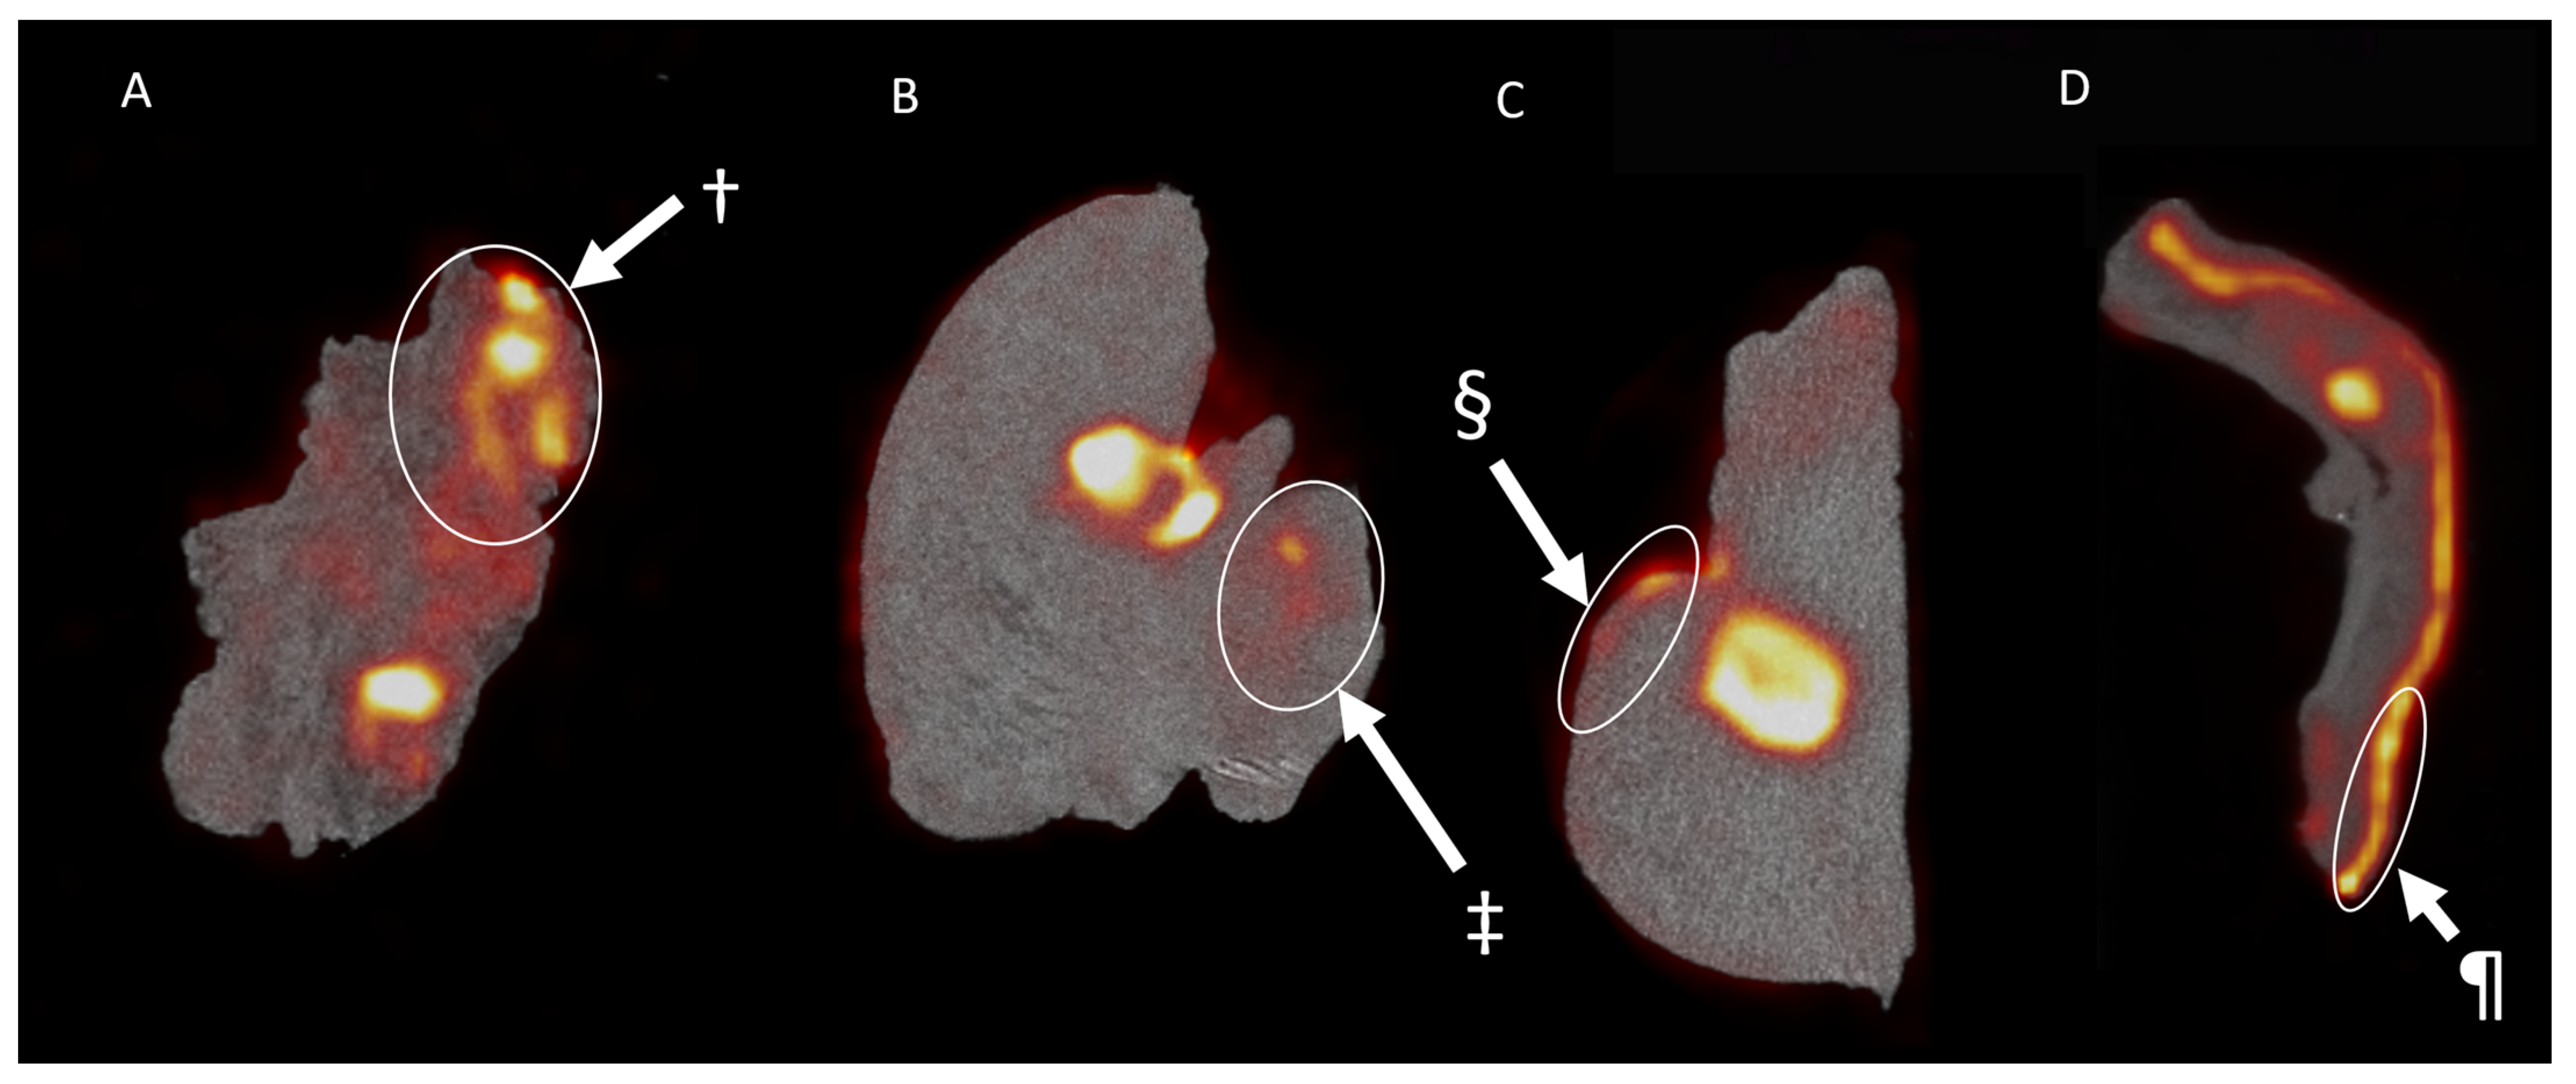

3.3. Pathology and Correlation with the Imaging Results

3.4. Lymph Nodes